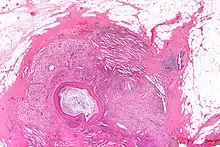

صورة مجهرية للحؤول الحرشفي للقنوات اللبنية بصبغة الهيماتوكسيلين والأيوزين